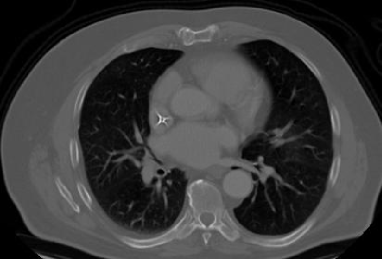

4.1.5 Chest CT

Chest CT scans play a relevant role in diagnosing a wide range of thoracic diseases, from infections to malignancies. By analyzing those scans, it is possible to detect diseases in the chest region, including pneumonia and cancer. The selected chest CT dataset 555https://www.kaggle.com/datasets/mohamedhanyyy/chest-ctscan-images contains 967 images across normal and three cancer types: adenocarcinoma, large-cell carcinoma, and squamous-cell carcinoma. Figure 6 provides a visual representation of the four highlighted classes.

Refer to caption

(a) Normal

(b) Adenocarcinoma

(c) Squamous cell carcinoma

(d) Large cell carcinoma

Figure 6: Chest CT scans.